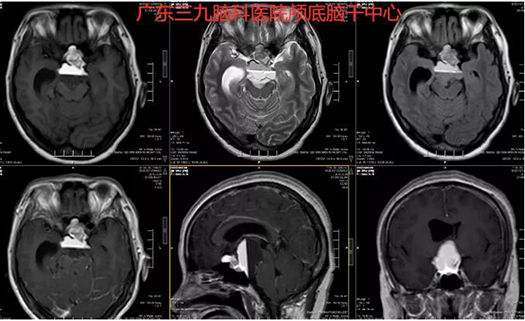

图1:术前MR示鞍上区示一不规则形占位性病变,其内示液-液平面,下层示长T1长T2信号,FLAIR相呈等信号,上层示短T1稍长T2信号,FLAIR相呈高信号。

图2:术前术后MR示呈术后改变,未见肿瘤征象。